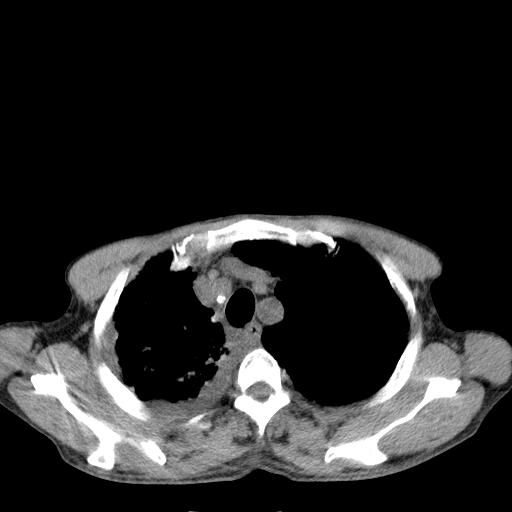

男性 75  咳嗽 一周前发热最高达39

右肺继发型tb并右侧tb性胸腔炎,右侧胸腔大量积液并右下肺膨胀不全,慢支肺气肿、多发肺大泡。建议抽胸水实验室检查并复查排除恶性在占位。

右上肺继发型肺结核,右胸腔中等量积液。

左上肺大泡。

结核的基础上有纵隔淋巴结肿大,右侧有胸水,但右侧纵隔反而窄,说明有肺有不张。

再就是右下肺有块影,和不张混合,还是不能除外肺癌。

1)右肺继发型肺结核。2)左肺胸膜下多发性肺大泡。3)右侧胸腔积液。